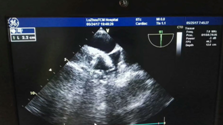

近日, 我院專家團隊通力配合,成功為一名78歲高齡的患者實施了左心耳封堵術。專家在患者左心耳置入了一個封堵器,從而有效地預防了患者發(fā)生房顫卒中的風險,據(jù)悉,這是川南地區(qū)成功開展的首例經(jīng)食道超聲指引下的“左心耳封堵術”。????? ?手術中?78歲高齡老人房顫致血栓???服藥無效??? ?? 江陽區(qū)一...